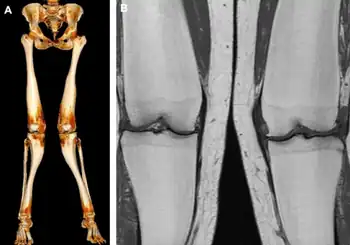

| a,b)MRI and CT of Pyle disease (metaphyseal dysplasia) | |

Metaphyseal dysplasia, or Pyle disease,[3] is a disorder of the bones. It is a rare disease in which the outer part of the shafts of long bones is thinner than normal and there is an increased chance of fractures. Its hallmark feature is an abnormality of the long bones in the arms and legs in which the ends (metaphyses) of the bones are abnormally broad; the shape of the bones resembles a boat oar or paddle. The broad metaphyses are due to enlargement of the spongy inner layer of bone (trabecular bone). Although trabecular bone is expanded, the dense outermost layer of bone (cortical bone) is thinner than normal. As a result, the bones are fragile and fracture easily. The bone abnormalities in the legs commonly cause knock knees (genu valgum) in affected individuals.